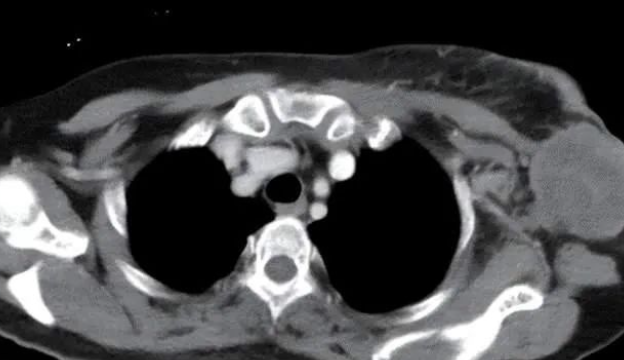

43岁陆女士,2019年5月无意间发现左乳肿块,未予重视,但随后肿块逐渐增大,而且伴有疼痛,于是便前往医院就诊,确诊为乳腺癌。

陆女士当前的情况无法实施根治性手术,尝试过化疗、中医调理等多种方法,肿块不仅没有缩小,还发生了转移。

考虑到陆女士目前已经出现多发转移,加上对化疗耐受性差,因此经过专家的商议,最终为制定了 NK细胞疗法,后来通过CT显示,胸壁肿块及腋窝淋巴结明显缩小,肺转移灶明显缩小。

经过多个疗程化疗后,疗效评估为部分缓解,无进展生存达10月后,胸壁病灶局部缓慢增大后联合放疗再次病情稳定,总的无进展生存达22个月。